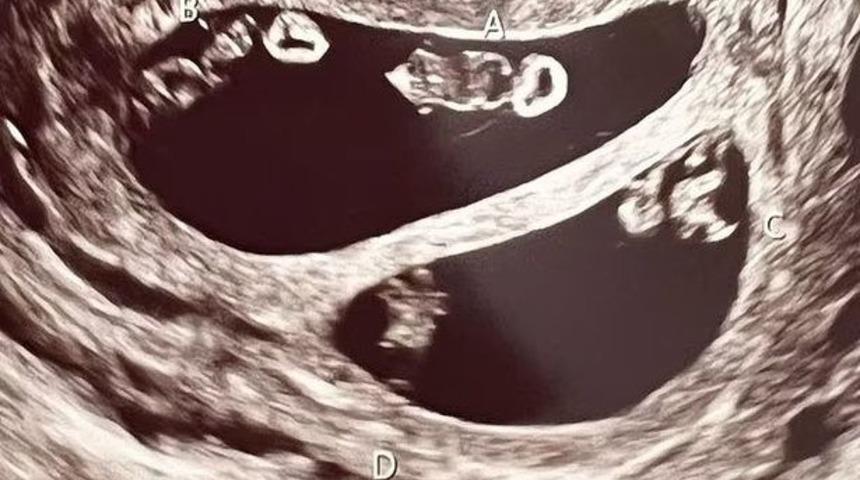

Hali hazırda bir kız evlat sahibi genç bir anne olan Ashley Ness, rutin bir kontrolde öğrendiği şey karşısında şoke oldu. İkinci çocuğunu beklediği için heyecanlı hisseden anne, Şubat ayında gittiği rutin kontrol esnasında karnında iki çift ikiz bebek taşıdığını öğrendi.

Doğurganlık sorunlarıyla mücadele eden Ashley doğal yollardan hamile kalmıştı. Karnında taşıdığı dört bebek dördüz değildi. Ashley tek yumurta ikizi iki kız ve yine tek yumurta ikizi iki erkek bekliyordu. Taramaya başladığında doktorunun da şoke olduğunu anlatan genç kadın, haberi ilk aldığında bayılacak gibi olduğunu anlattı.